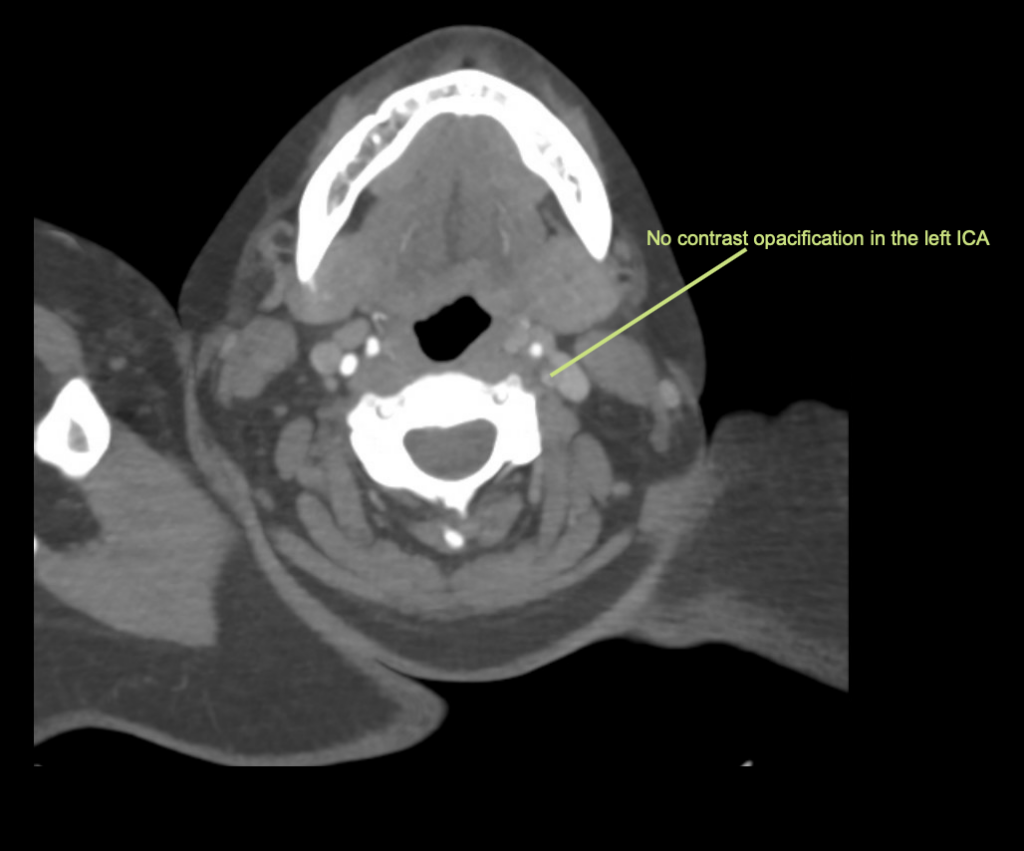

Vengono eseguiti una TAC cerebrale, un angiogramma e una scansione della perfusione cerebrale.

Descrivi e interpreta la TAC

Interpretazione della TAC